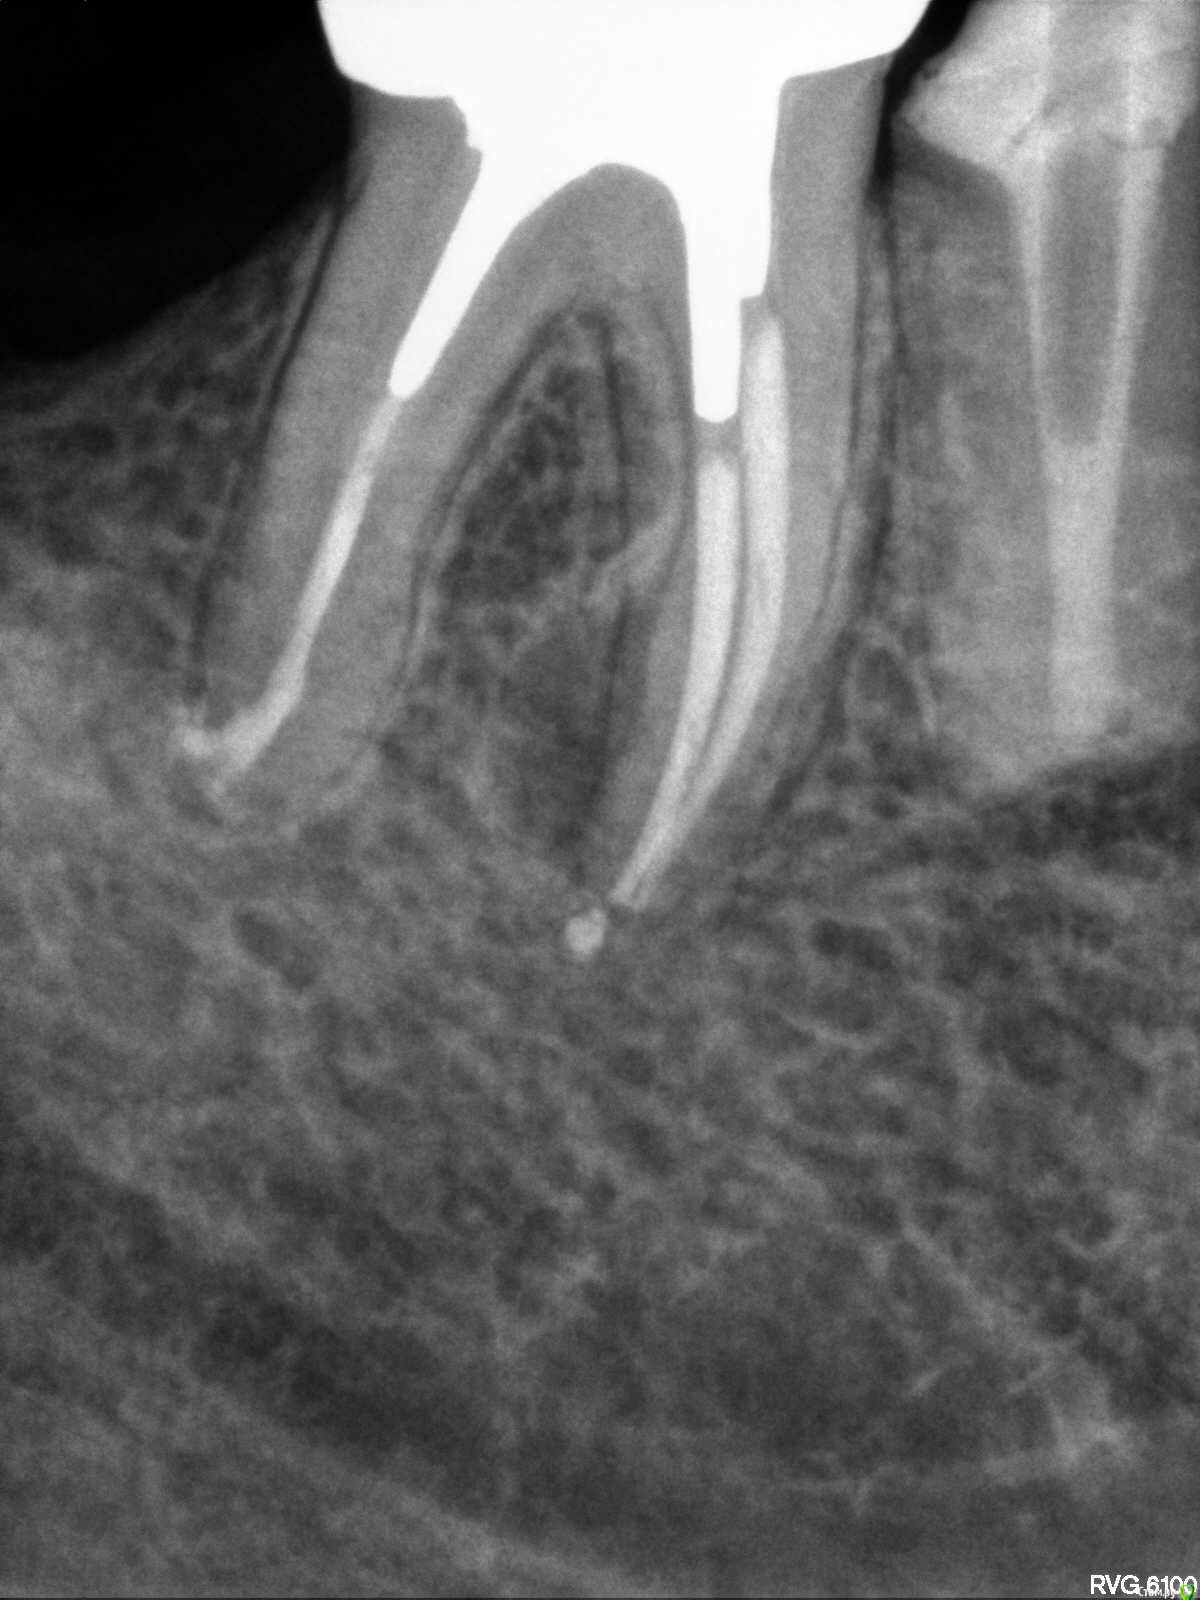

Placeforastep Опубликовано 11 февраля, 2021 Поделиться Опубликовано 11 февраля, 2021 Добрый день! Подскажите пожалуйста, есть ли на корне периодонтит ? Ссылка на комментарий

Placeforastep Опубликовано 13 февраля, 2021 Автор Поделиться Опубликовано 13 февраля, 2021 Здравствуйте, что Вас беспокоит?Беспокоит хроническая боль/зуд в районе этих двух зубов (5 и 6 нижние зубы). Усиливается к вечеру , ночи и особенно сильно по утрам . Так уже 6 лет. Это долгая история. Просто хотел получить второе мнение есть ли на 6 зубе признаки периодонтита. Ссылка на комментарий

annda Опубликовано 14 февраля, 2021 Поделиться Опубликовано 14 февраля, 2021 (изменено) Не походит на боли при периодонтите. Изменено 14 февраля, 2021 пользователем annda 1 Ссылка на комментарий

red_butler Опубликовано 15 февраля, 2021 Поделиться Опубликовано 15 февраля, 2021 Ничего плохого на rg не увидел Ссылка на комментарий